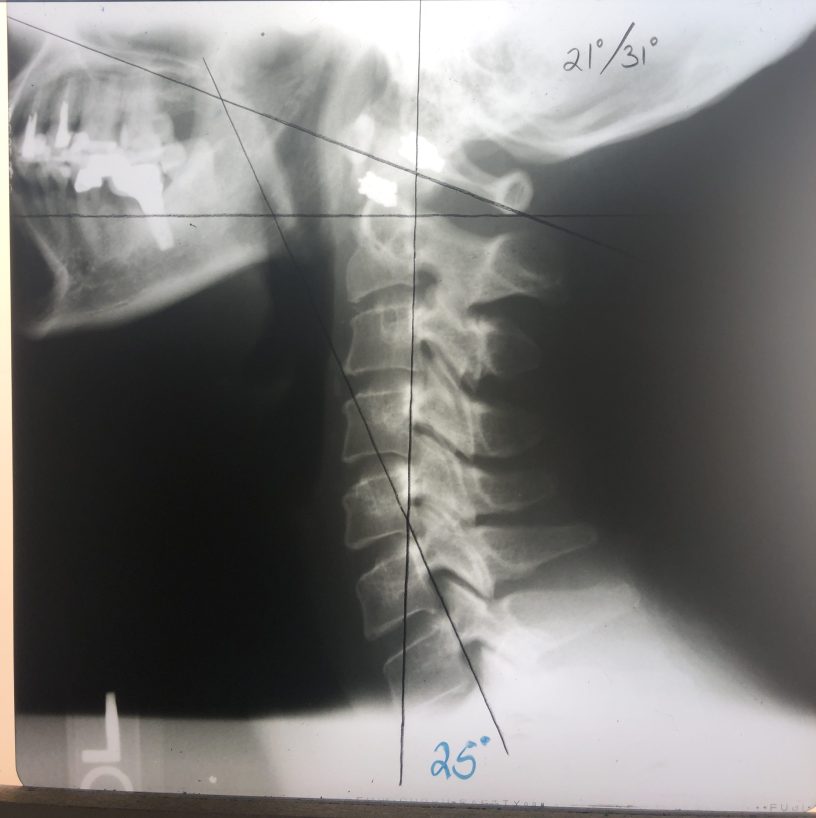

The normal curve for the neck is 45 degrees, shape like a banana.

My neck curve was -5 three months ago (14 degrees/31 degrees) and now is +25 degrees (21 degrees/31 degrees).

我是去年11月開始的, 12月回臺灣一個月, 然後今年的一月和二月, 每週三到四次的整脊, 可能我本身的健康狀況還不錯吧, 所以第一個月結束時並沒有很大明顯的轉變, 但是睡眠似乎有好一些, 然後我就回台灣了, 但是當我從台灣回來後, 很多朋友都說我瘦很多 (可是我也沒有運動, 在台灣的飲食你也知道, 完全沒在控制), 回美後又開始每週三到四次的整脊, 一月後我就開始早上會想排便, 雖然沒有每天, 但是一週有三四天也算是很大的進展, 然後開始覺得有精神, 情緒也變得穩定很多 (開始冥想打坐也有幫助), 然後二月又過去了, 終於到了要再拍脊椎X光片, 看看三個月的成效, 結果我的頸椎從負五度變成正25度 (雖然離健康的正45度還有一點距離), 胸椎和頸椎也非常接近正常的位置, 醫生比我還高興, 他們蠻驚訝我頸椎的進步程度 (該做的脊椎運動我都沒有乖乖做, 所以這樣的結果我很滿意了).